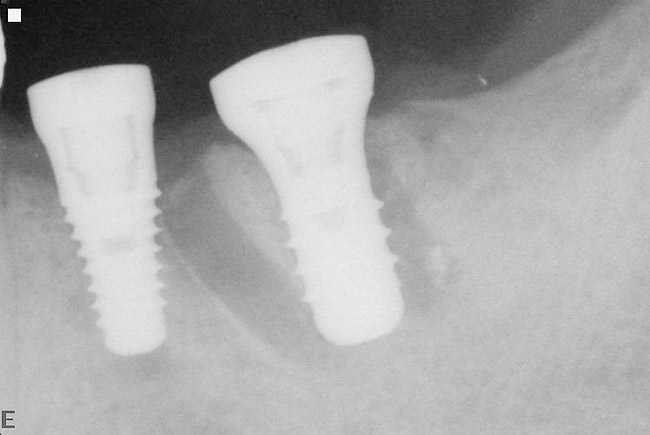

Figure 18  Following hemisection and extraction of the hopeless molar, implants were placed in the first and second molar positions, utilizing specific interradicular bone preparation techniques. Note the positioning of the implant in the second molar site so as to provide adequate dimension for ideal placement of an implant in the first molar area.

Figure 18

Figure 19  A radiograph taken after 46 months in function demonstrates the stability of the crestal peri-implant bone around both implants.

Figure 19